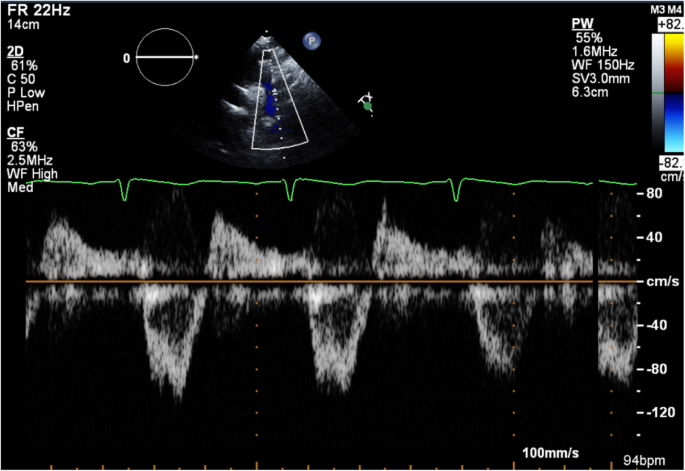

Transthoracic echocardiography (TTE) was subsequently performed for investigation of the new continuous murmur – other conditions apart from an SVA which can present with continuous murmurs include; patent ductus arteriosus, coarctation of the aorta, coronary arteriovenous fistulas and an aortopulmonary window. TTE showed normal left and right ventricular size and systolic function. To the unwary eye, the colour flow at the RV inflow view may appear like tricuspid regurgitation. However, the continuous wave Doppler clearly demonstrated a continuous wave form throughout systole and diastole (Fig. 1, Videos 1 and 2). Additionally, a significant left-to-right shunt was detected on the colour Doppler between the right coronary sinus and the right atrium (Fig. 2, Video 3). Interestingly, Doppler echocardiography detected diastolic flow reversal in the thoracic descending aorta which is more commonly seen in severe aortic regurgitation (Fig. 3).

Limitations of TTE were present in our case, in which the exact path of the shunt was difficult to demonstrate whereas TOE was very accurate for establishing a diagnosis. Additionally, TTE was suspicious for tricuspid regurgitation whereas TOE confirmed normal tricuspid valve anatomy and function. The demonstrated diastolic flow reversal in the descending thoracic aorta occurs due to the significant left-to-right shunt from the aortic root to the right-sided cardiac chamber creating similar haemodynamic physiology as severe aortic regurgitation.